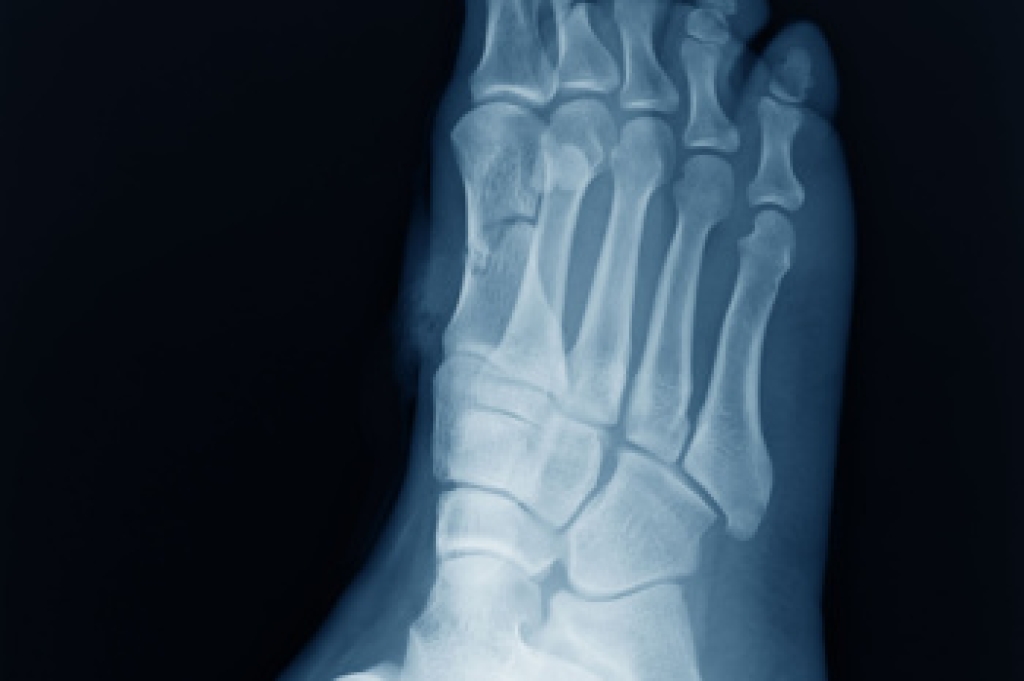

Morton's neuroma is a painful foot condition that commonly affects the areas between the second and third or third and fourth toe, although other areas of the foot are also susceptible. Morton’s neuroma is caused by an inflamed nerve in the foot that is being squeezed and aggravated by surrounding bones.